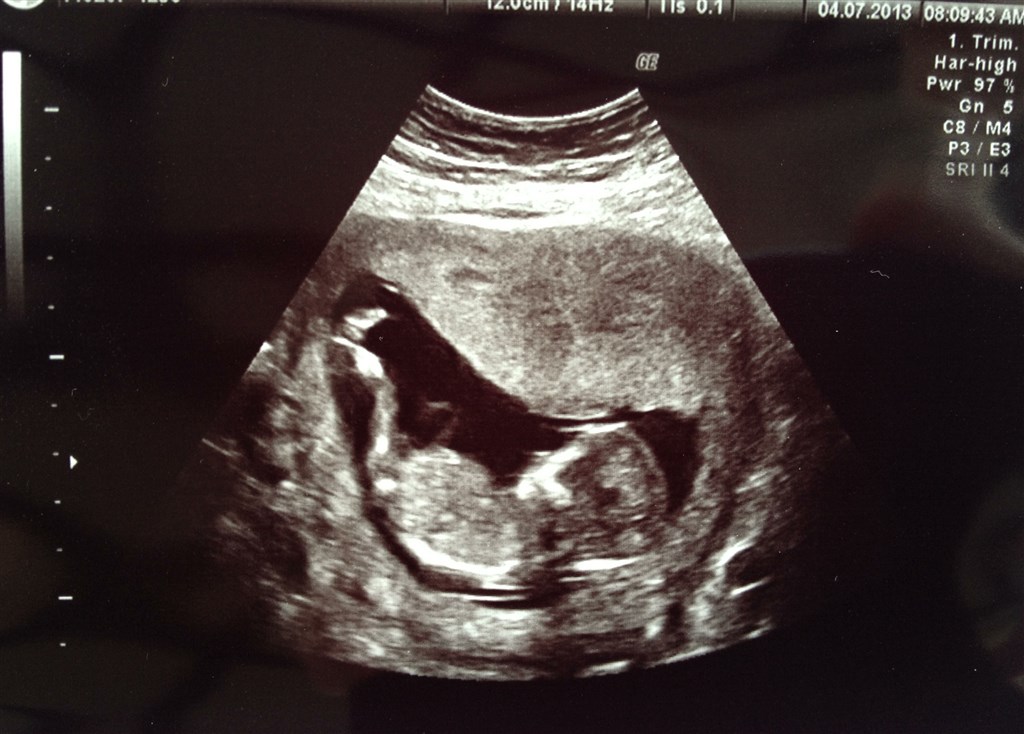

Så er vores nf også veloverstået, det var så dejligt, at se liv i den lille og at se det lille hjerte banke. Fantastisk følelse.

Vores risiko hedder 1 : 18.094, så ingen bekymring der. Med vores datter Laura hed den 1 : 20.564, men det er også 3,5 år siden, så mon ikke det er derfor

og så rykkede hun min termin til 10/1, hvor den før hed 14/1.

Her et billede af vores lille vinterbaby med lange ben